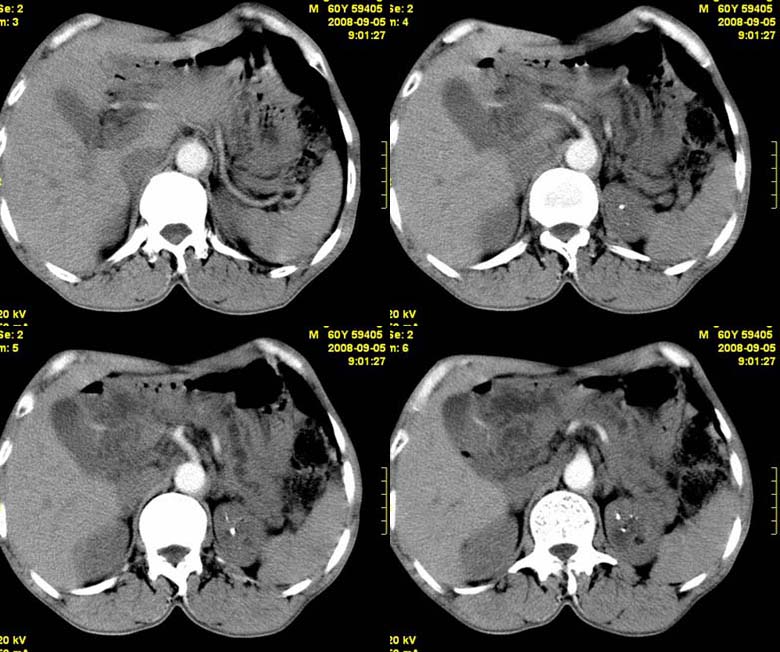

标题: CT15580:M60Y,胰腺病变,平扫+增强 [打印本页]

标题: CT15580:M60Y,胰腺病变,平扫+增强

患者,男, 60,既往有间歇腹痛病史多年,现右上腹痛,加重一月,伴右后背部疼痛,无黄疸,无发热。

考虑胰腺囊腺瘤或慢性胰腺炎

胰头区增大,胰管明显扩张,不均匀强化,且与 周围结构不清,后背疼痛,考虑为胰腺头部胰腺癌。

胰头囊腺癌

胰头囊腺癌

慢性胰腺炎

胰头囊腺癌

慢性胰腺炎并胰头癌